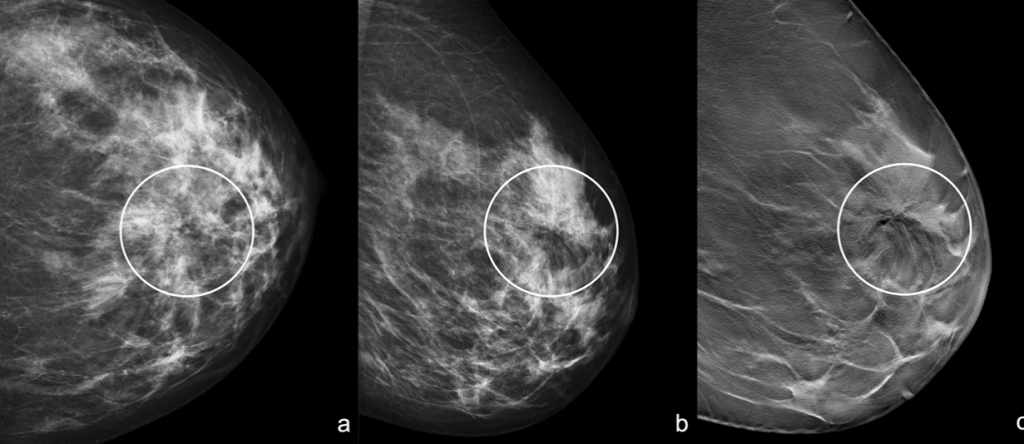

“Black Star”: Left craniocaudal (a) and mediolateral oblique (b) mammograms show an area of architectural distortion with radiolucent core in the union of upper quadrants (white circle). Left mediolateral oblique tomosynthesis (c) confirms the area of architectural distortion and shows better the radiolucent core with the radiating long thin spicules (white circle)